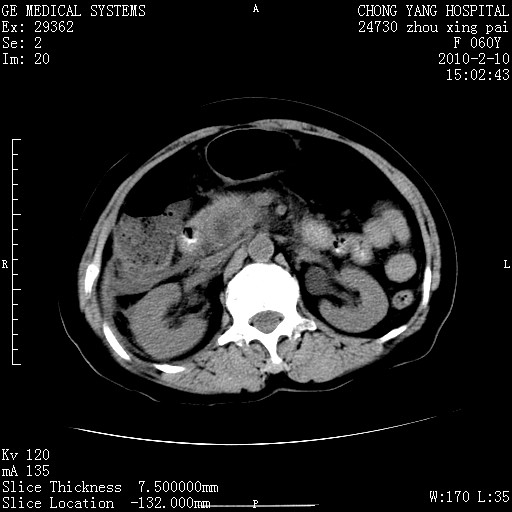

标题: CT24682:F60Y 腹痛 其它不详 [打印本页]

标题: CT24682:F60Y 腹痛 其它不详

胆总管末端梗阻!结石?胰腺影增粗,以胰腺头部为著,胰周看见渗出影,双侧胸腔积液,(胸膜反应)考虑胰腺炎。

1)胆总管末端梗阻,不排除结石所致可能。2)胰腺炎。3)慢性胆囊炎可能。4)左侧输尿管上段扩张。5)少量腹水。6)双侧少量胸腔积液,伴两下肺部分肺萎陷。

1)胆囊炎。2)胆源性胰腺炎。3)右肾周筋膜增厚,肾旁前间隙积液。4)左侧输尿管上段扩张。5)少量腹水。6)双侧少量胸腔积液,伴两下肺部分肺膨胀不全。

1)胆总管末端梗阻。2)胰腺炎。3)慢性胆囊炎可能。4)左侧输尿管上段扩张。5)少量腹水。6)双侧少量胸腔积液,伴两下肺部分肺萎陷。